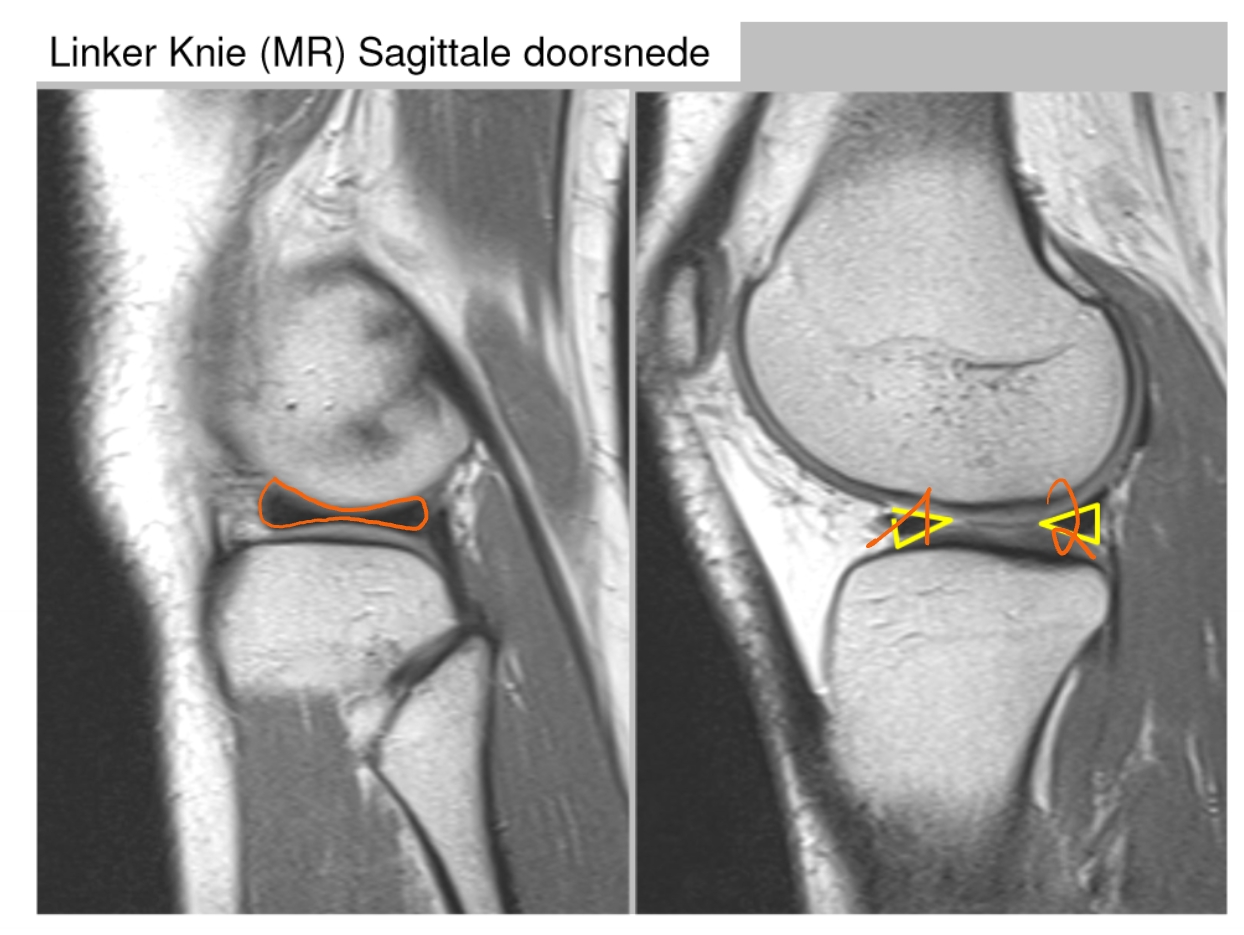

→ linker knie (MR): dwarse doorsnede

meniscus

anterieur

posterieur

pees van de m. quadriceps

patellapees

vetweefsel van Hoffa

voorste kruisband

achterste kruisband

meniscus (anterieur)

meniscus (posterieur)

tractus iliotibialis

mediaal collateraal ligament

lateraal collateraal ligament

→ linker knie (MR): coronale doorsnede